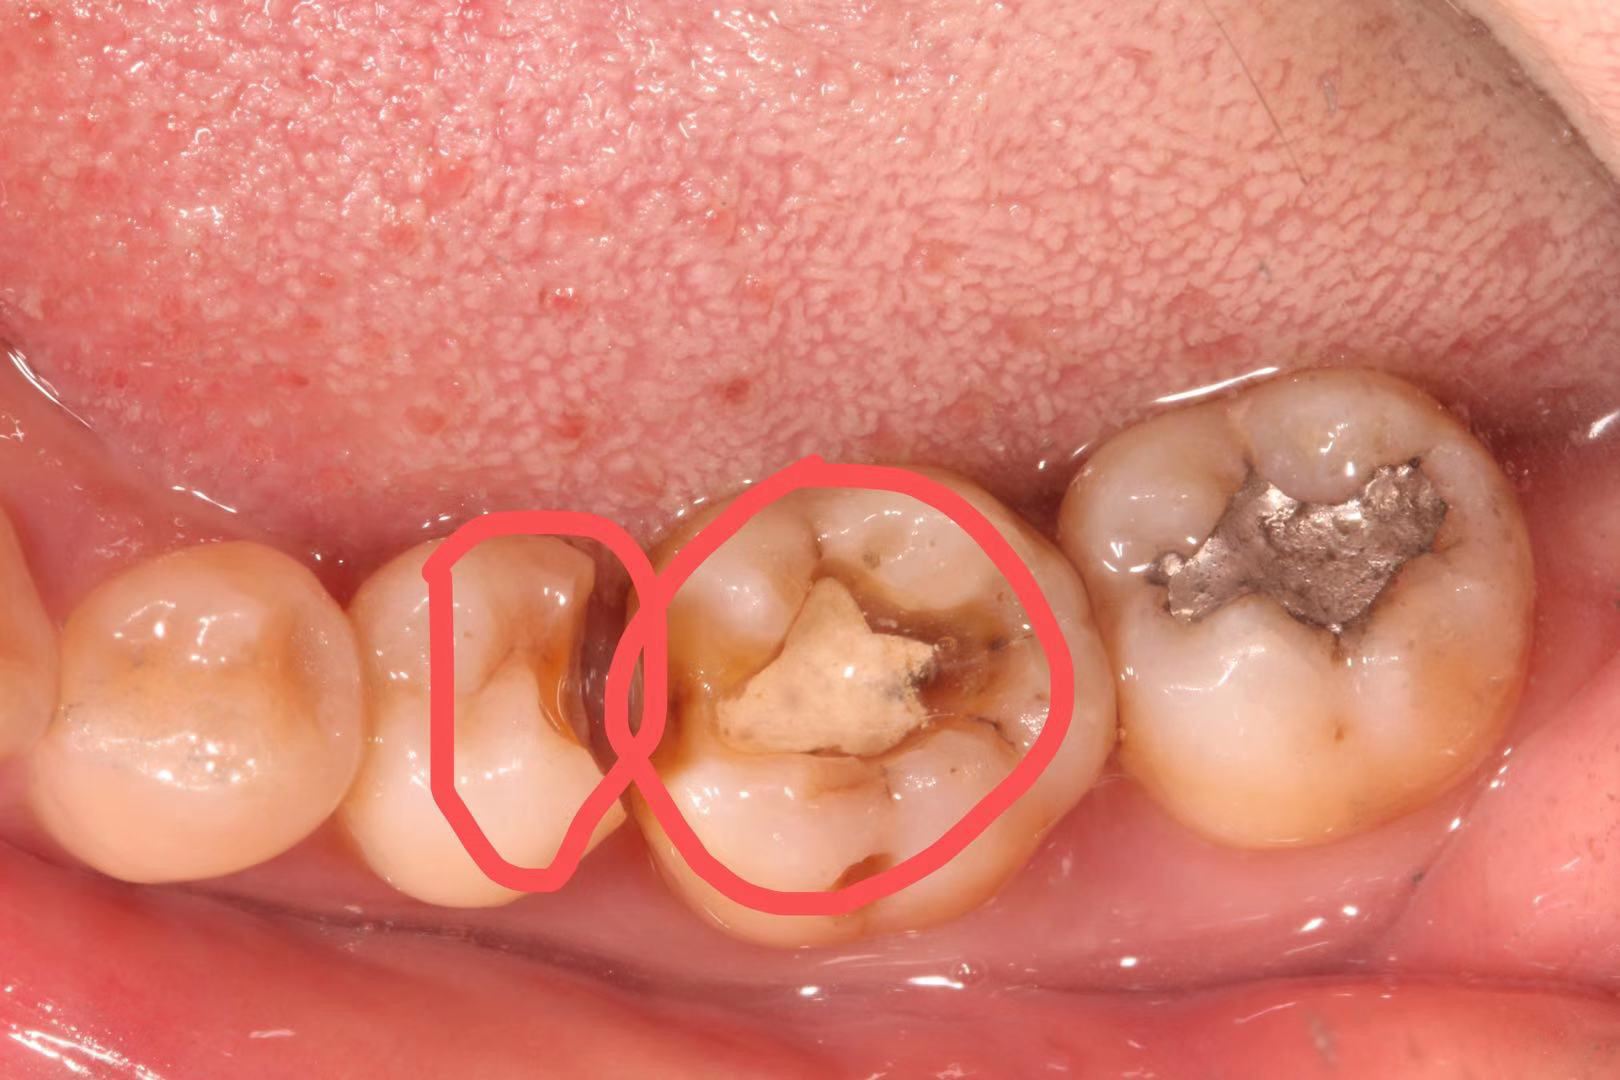

患者多年前银汞充填,因边缘微渗漏导致继发龋坏,我院采用相较于传统补牙更耐用、美观、可承受更大咬合力的修复方式:嵌体修复。

治疗步骤:1 去净龋坏, 2 制备洞形,3 扫描,4 切割制作,5 戴牙。